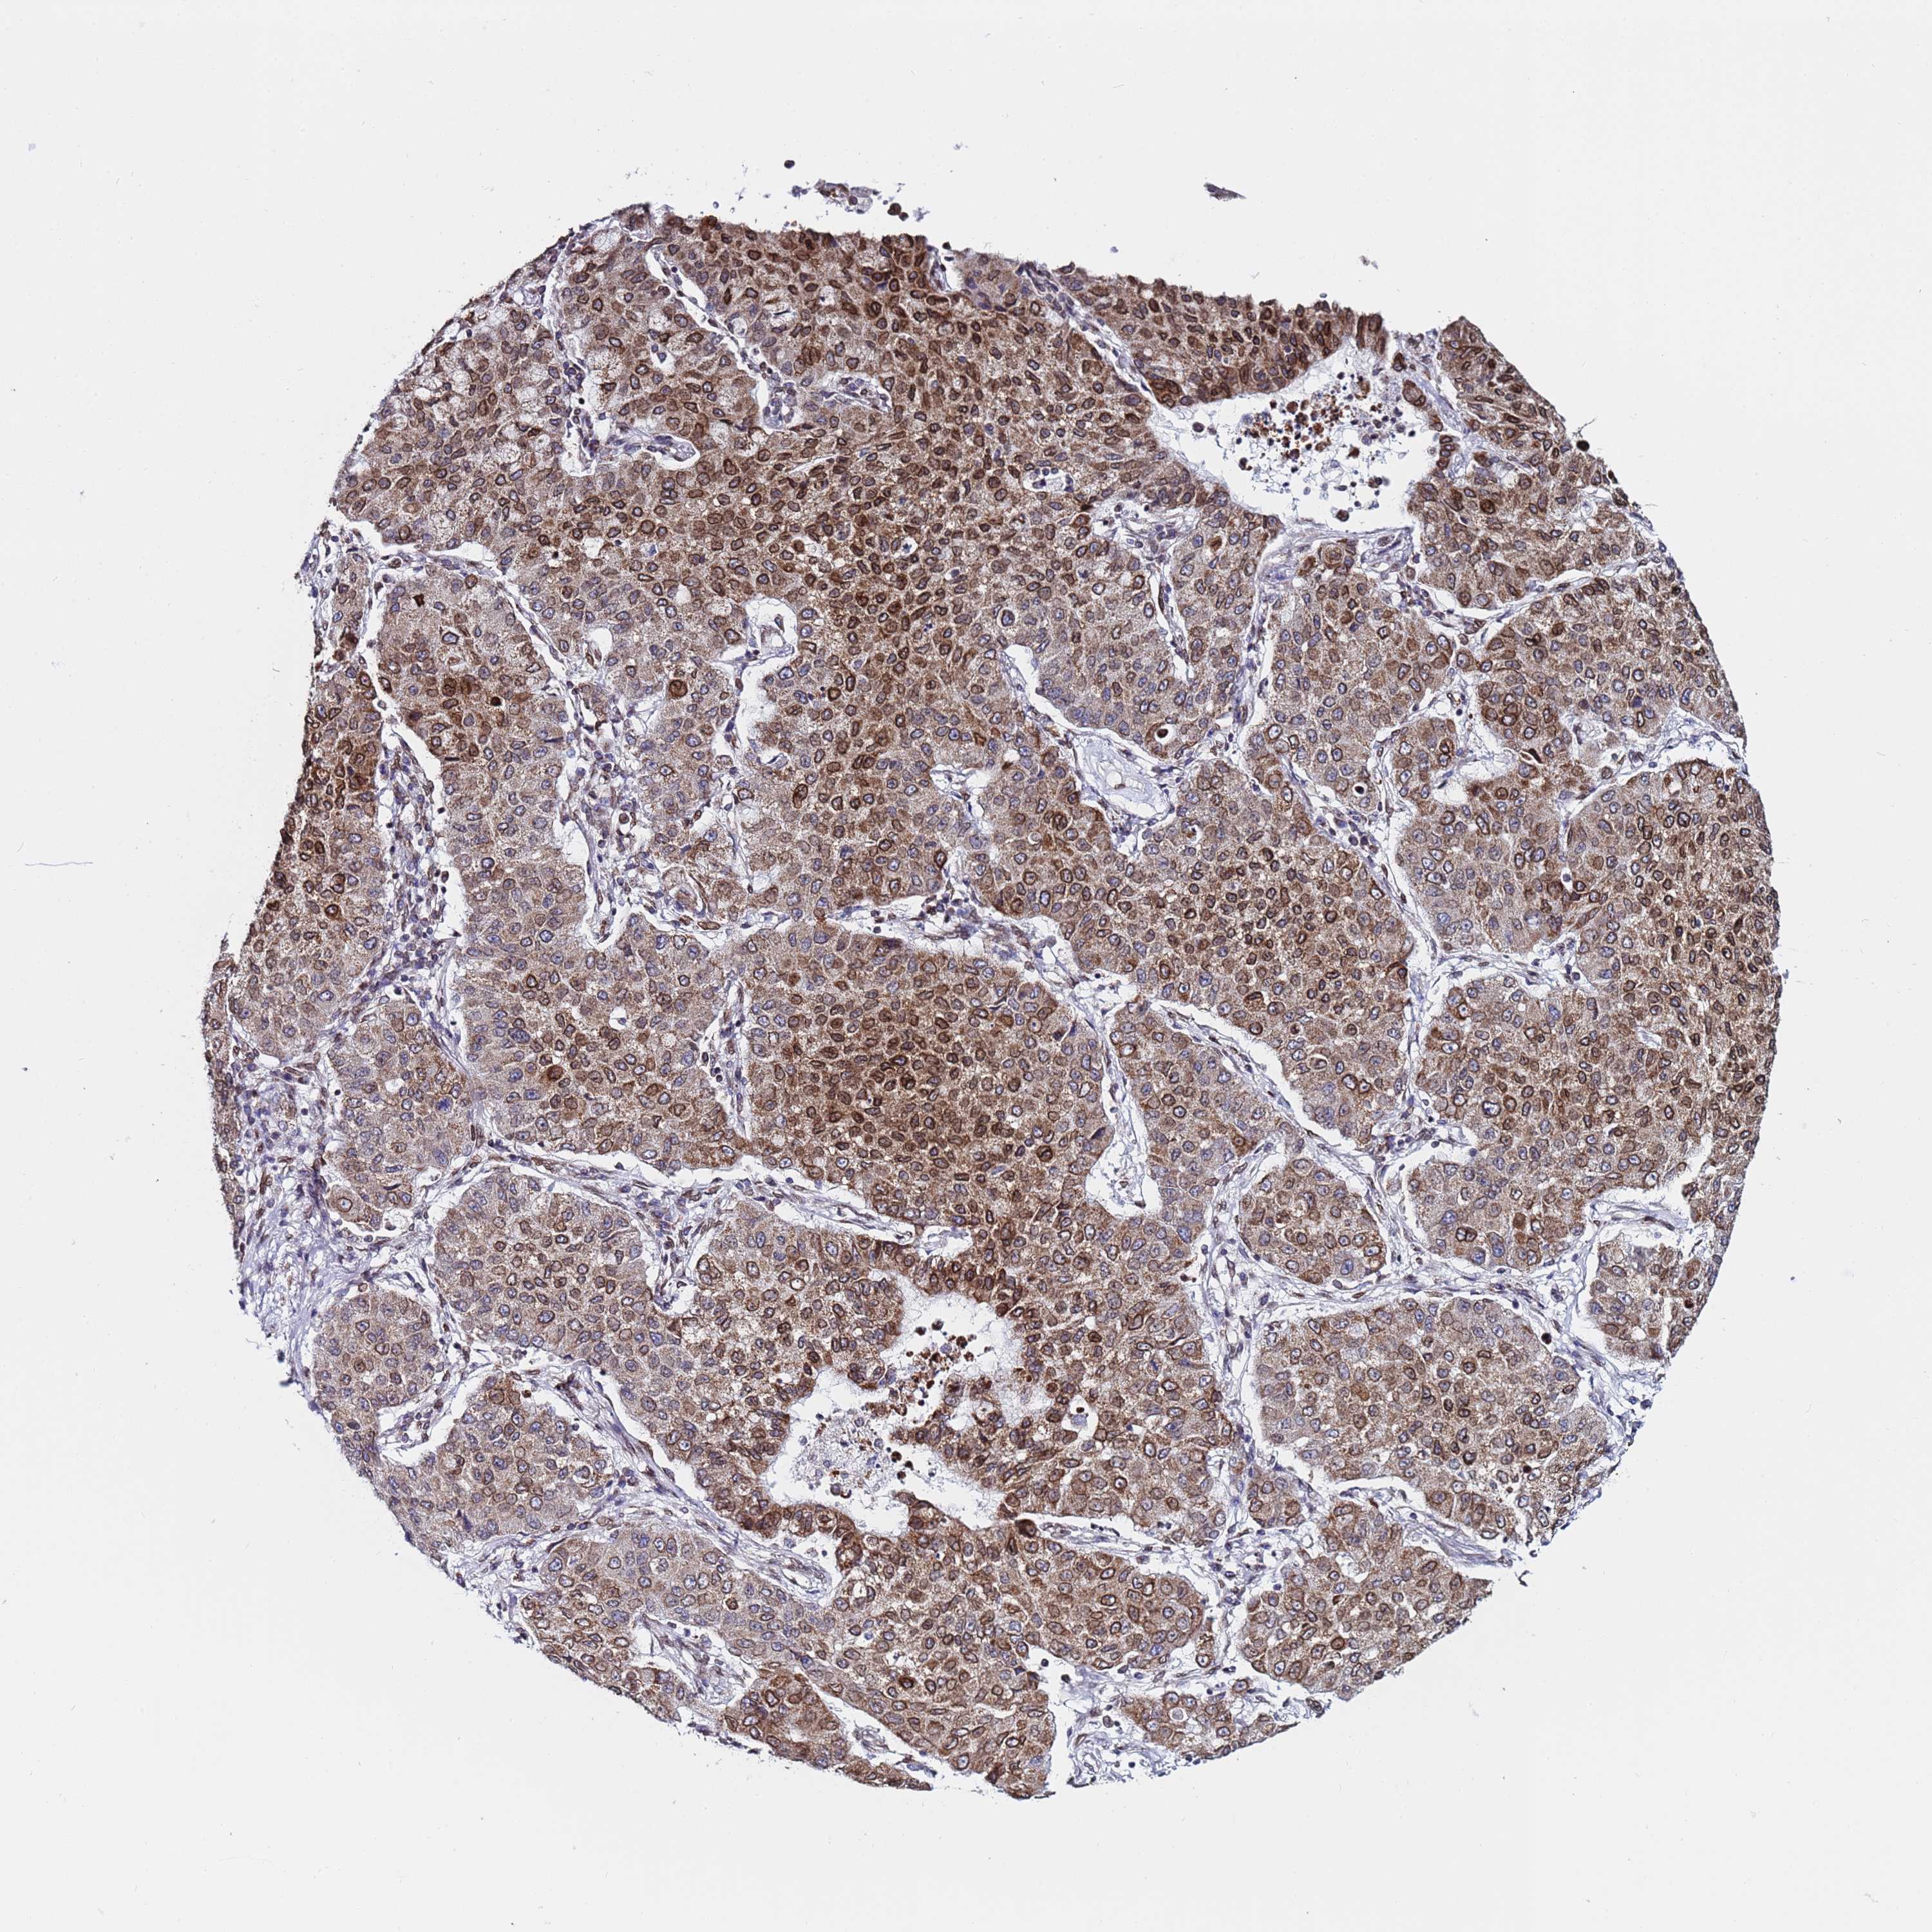

CANCER LUNG CANCER Show tissue menu

LUAD TCGA LUAD VALIDATION LUSC TCGA LUSC VALIDATION PROTEIN LUAD CPTAC PROTEIN LUSC CPTAC PROTEIN EXPRESSION

TOR1AIP1 is not prognostic in Lung Adenocarcinoma (validation)

Average pTPM 51.3

Number of samples 105